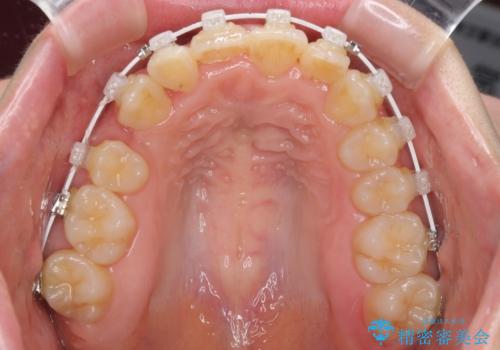

- 右上の八重歯と、左下八重歯を抜いてしまったことを気にして来院された患者様です。

下顎は既に犬歯を1本抜歯しているため、上顎右側第一小臼歯を抜歯し、ワイヤー装置にて歯列を整えることとしました。

変則的な抜歯となるため、正中と人中がずれる可能性がありましたが、仕上がりは上下正中を揃えることができました。